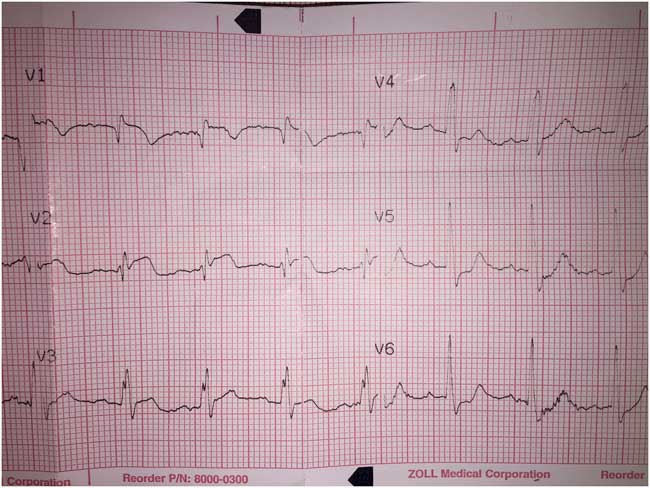

We present the case of a previously well 41-year-old male who presented to our emergency department (ED) after a witnessed syncopal episode. No further history was immediately available. A pre-hospital echocardiogram (ECG) showed ST-segment elevation in leads V1–V3 (Figure 1). Consequently, the patient was accepted to the ST-elevation myocardial infarction (STEMI) ED bypass protocol by our hospital and was being transported for immediate coronary angiography.

Figure 1 Pre-hospital ECG strip, initially interpreted as anterior ST-elevation MI by our hospital’s STEMI bypass program.

Anterior ST elevation, noted in our patient’s pre-hospital ECG, is uncommon in acute PE, though it has been described.Reference Livaditis, Paraschos and Dimopoulos 11 , Reference Lin, Lin and Yang 15 , Reference Falterman, Martinez, Daberkow and Weiss 16 Proposed mechanisms include right ventricular strain and injury because of increased afterload; rarely, this finding can reflect coronary occlusion due to a clot through a patent foramen ovale.Reference Lin, Lin and Yang 15 , Reference Cheng 17 It is often visually indistinguishable from the ST elevation seen in an acute myocardial infarction; however, the simultaneous (or subsequent) presence of more specific ECG findings may raise the index of suspicion for PE at a patient’s bedside.Reference Lin, Lin and Yang 15 In patients with cardiogenic shock, anterior T-wave inversions and ST elevation in leads aVR and V1 are associated with PE.Reference Ferrari, Imbert and Chevalier 12 , Reference Kukla, McIntyre and Fijorek 18